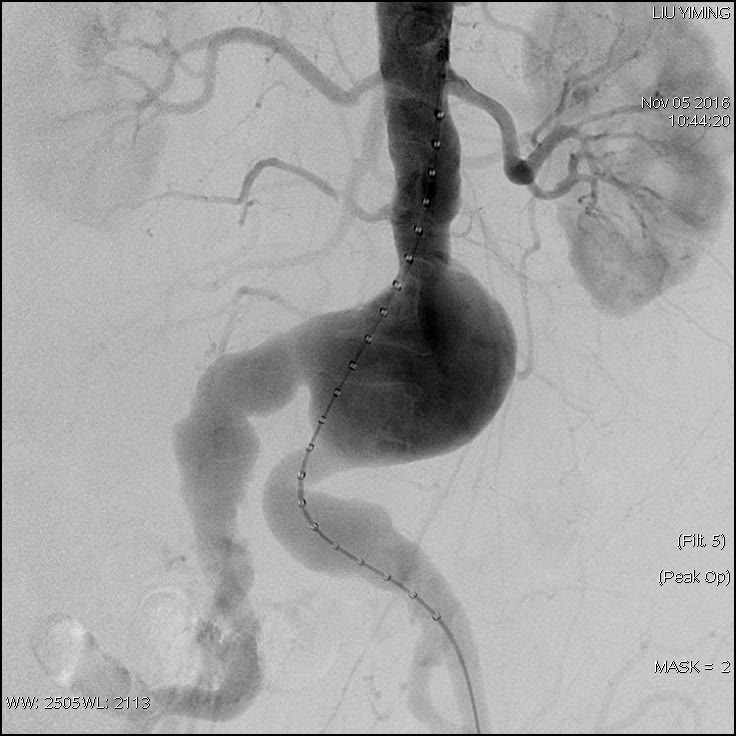

其中,在复杂主动脉病变腔内修复术应用手术直播中,郭伟教授带领其团队使用先健科技公司的髂动脉分叉支架系统(IBD)以完全腔内重建的方式成功修复复杂腹主动脉瘤及髂动脉瘤。该例手术患者为64岁的男性,被诊断为肾下腹主动脉瘤,瘤体最大直径约6.5cm,双侧髂动脉瘤。患者成功植入先健科技IBD支架,定位准确,无内漏,成功保留了左侧髂内动脉,术后造影显示髂内动脉通畅。

图:术前造影、术中造影、术后造影